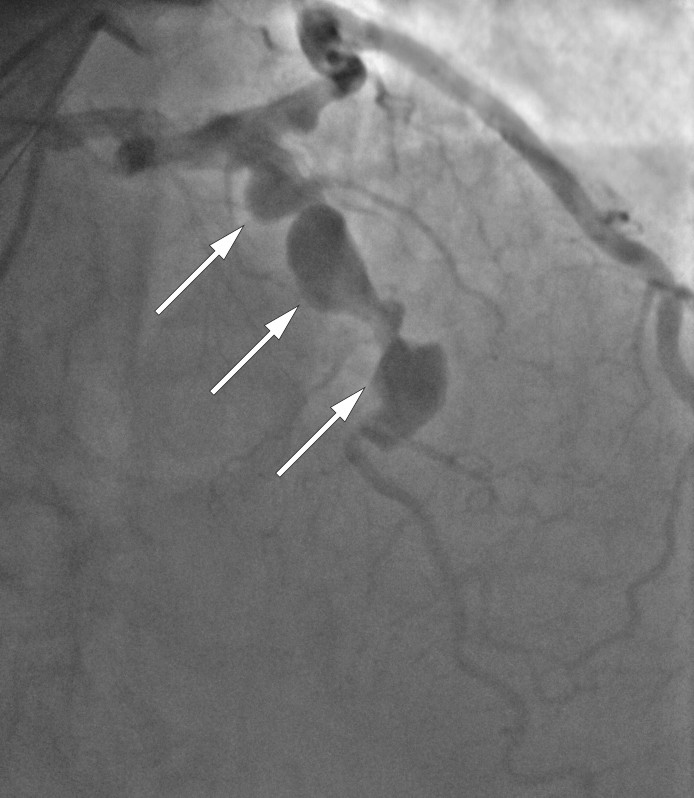

En etnisk norsk mann i 60-årene med hypertensjon, dyslipidemi, betydelig røykeanamnese og tidligere iskemisk hjerneinfarkt gjennomgikk en prehospital hjertestans med ventrikkelflimmer som første registrerte hjerterytme. Han ble resuscitert og brakt til koronarangiografi. EKG etter resuscitering var forenlig med ST-elevasjonsinfarkt i nedre vegg. Ved undersøkelsen fant man trombotisk okklusjon i midtre avsnitt av høyre koronararterie samt spredte aterosklerotiske forandringer i både høyre og venstre koronararterie. I tillegg hadde pasienten flere aneurismer i alle tre koronarkar (figur 1).

Pasientens trombotiske koronarokklusjon ble revaskularisert med perkutan koronar intervensjon, og det ble startet sekundærprofylaktisk behandling for å redusere risikoen for fremtidige koronare hendelser. Som ledd i videre utredning ble det gjennomført CT aortografi med følgende funn: Ektasi av aorta ascendens, med største diameter 43 mm i nivå med truncus pulmonalis, et infrarenalt abdominalt aortaaneurisme med største diameter 32 mm, samt ektasi av arteria iliaca communis bilateralt (figur 2). CT-funnene ga ikke indikasjon for intervensjon, og det ble avtalt oppfølging ved kardiologisk og karkirurgisk avdeling for kontroll av henholdsvis koronarsykdom og aortaaneurismer.